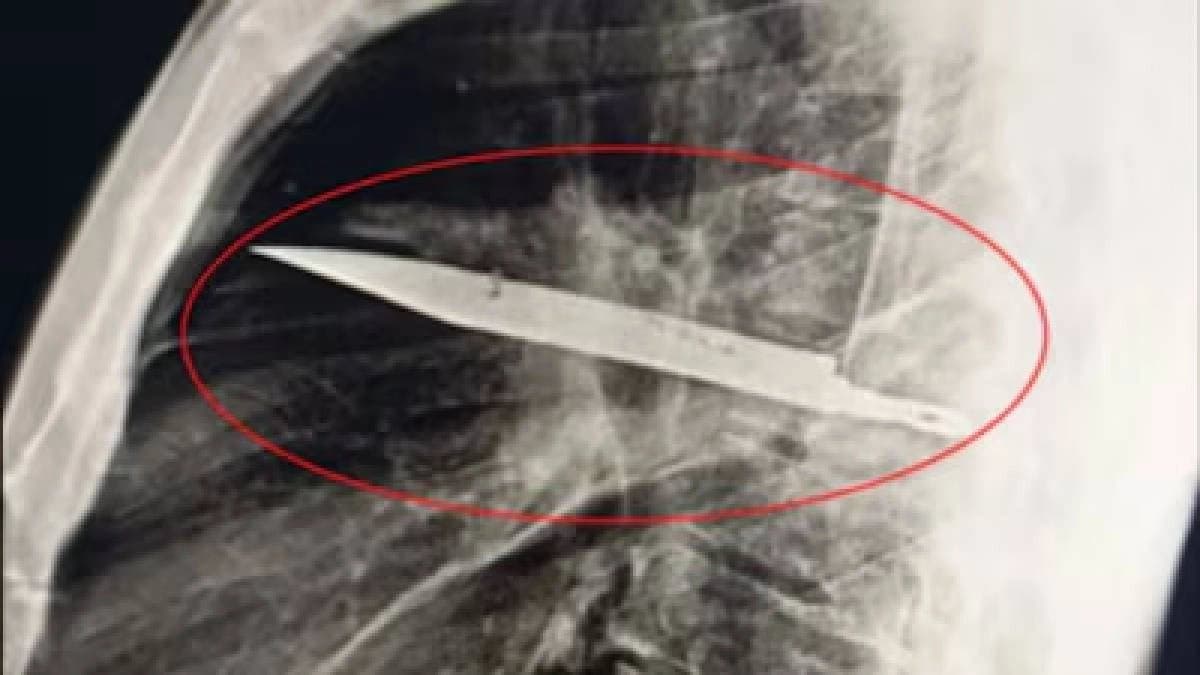

ব্যক্তির স্তন বৃন্তে ৮ বছর ধরে 'লুকিয়েছিল' ছুরি! 'হিয়ার' মাঝে লুকিয়ে থাকা যৌন ধাঁধা আপনাকে বিস্মিত করবে